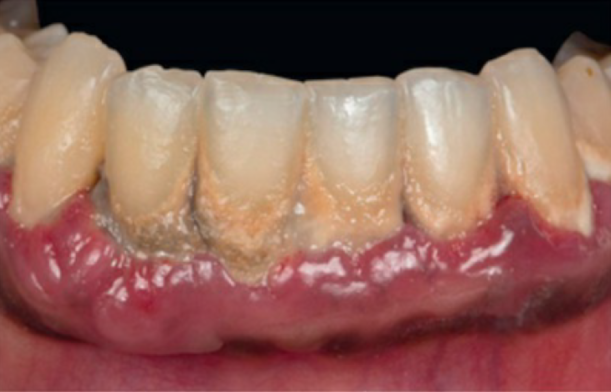

Jau 1960 metais buvo nustatyta, kad periodontas labiausiai kenčia dėl susikaupusių apnašų. Žmogaus burnoje galima aptikti maždaug šeši šimtus rūšių bakterijų: dalis jų neturi neigiamo poveikio sveikatai, tačiau kai kurios bakterijos gali sukelti įvairius negalavimus. Jei nesirūpinama tinkama dantų ir dantenų higiena, ima kauptis apnašos, iš kurių vėliau susiformuoja dantų akmenys. Nors patys dantų akmenys nesukelia periodonto ligų, tačiau jų šiurkšti ir porėta tekstūra sudaro palankesnes sąlygas kauptis bakteriniam apnašui. Ilgainiui tarp dantų ir dantenų atsiranda tarpeliai, kurie vadinami dantenų kišenėmis. Atsiradus šiai patologijai bakterijos ima dar sparčiau daugintis, todėl išsivysto uždegimas, apimantis gilesnius audinius ir žandikaulio kaulą. Ligos eigai įtakos turi imuninė sistema – jei periodontitas nėra laiku gydomas, šis susirgimas didina širdies susirgimų riziką, gali neigiamai paveikti diabeto eigą ar lemti priešlaikinį gimdymą.

Periodontologas visada vertina paciento burnos būklę ir sudaro individualų gydymo planą. Jei nėra diagnozuojami negrįžtami pakitimai, kartais tereikia atlikti profesionalią burnos higieną ir nuvalyti viršdanteninius ir podanteninius akmenis. Jei procesas pažengęs atleikamas giluminis valymas (dantenų kiuretažas) su uždegimo pažeistų dantenų konservatyviu pašalinimu. Ypatingai sunkiais atvejais atliekama atliekama lopo operacija, kai pašalinamas didelis kiekis pažeistų dantenų, žandikaulio defektai gali būti užpildomi kaulo užpildais. Šiuolaikinė periodontologija užtikrina, kad pacientui atliekamos procedūros nesukels pernelyg didelio diskomforto – visuomet yra taikomas nuskausminimas.